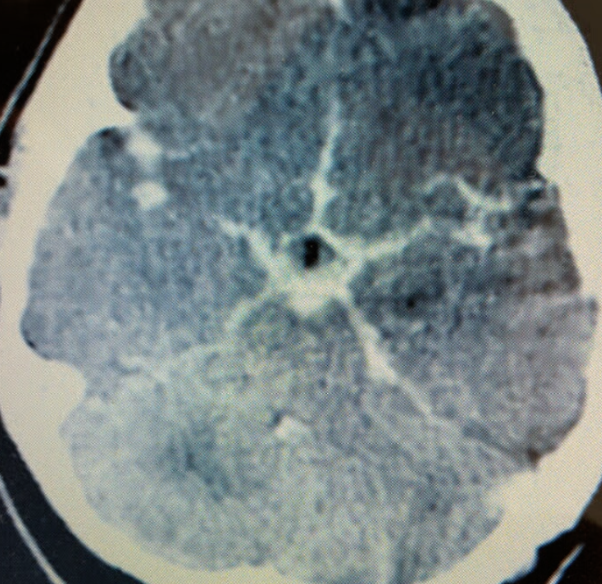

1. What is the abnormality in the image shown?

a. Blood mixed with CSF filling the subarachnoid space

2. What is the likely diagnosis?

a. Subarachnoid hemorrhage

3. What is the abnormality in the image shown?

b. Hyper dinse lesion

4. What is the likely diagnosis?

a. Meningitis